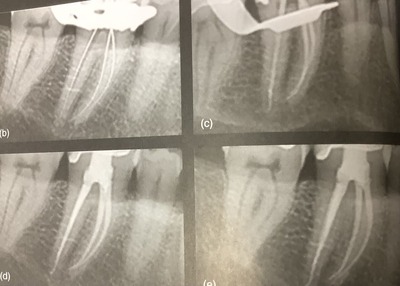

CBCTは何を教えてくれるのか?

根っこの長さについても、CBCTがあれば正確に教えてくます。

前後の重なったものをどけて見れるのでね。

もちろん、根っこの先の状態も神経の形や特徴も良く分かりますし。

複雑な歯には本当に有効です。

神経への入り口を開けて、少し広げます。

根っこに長さ、作業長を決めて削っていきます。

一年後のレントゲンでは、すっかり良くなってます。